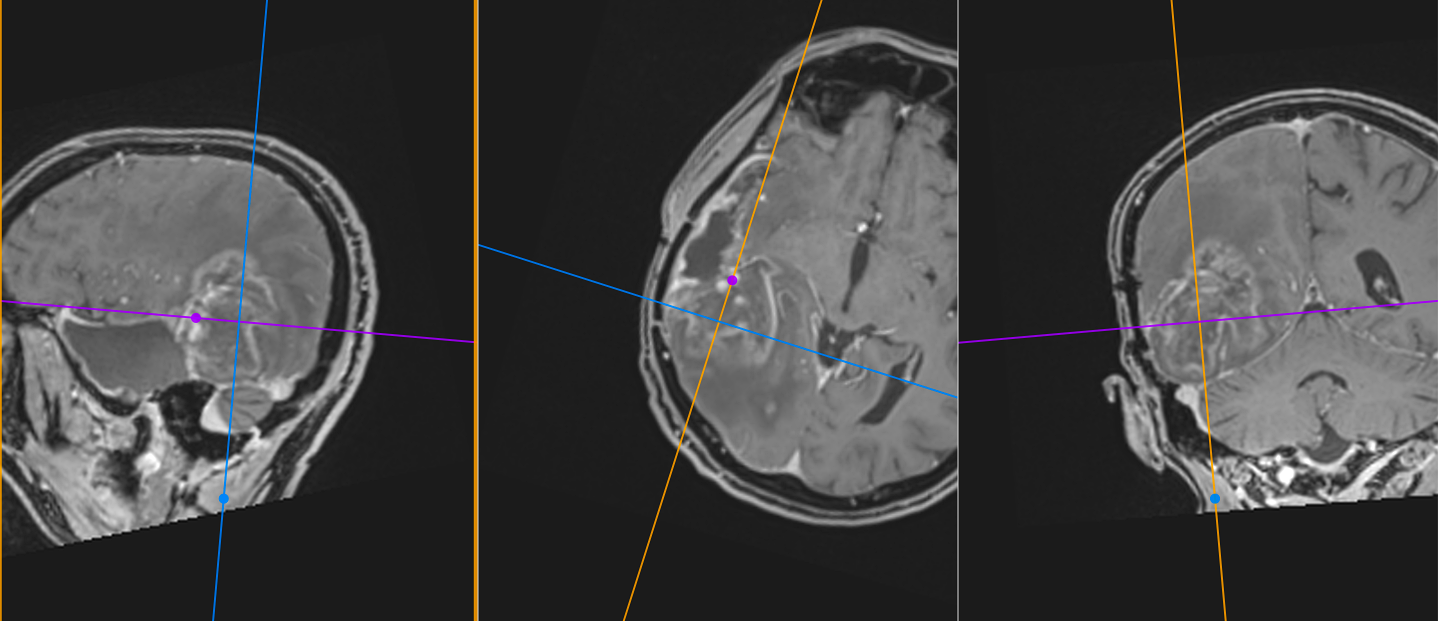

Imagistica – instrument esențial, dar imperfect

RMN-ul cerebral este standardul diagnostic, dar trebuie interpretat în context.

Pe lângă secvențele convenționale, tehnicile avansate aduc informații suplimentare:

- perfuzia evidențiază angiogeneza tumorală

- spectroscopia reflectă metabolismul celular

- DTI (tractografia) arată relația cu tracturile din substanța albă

Cu toate acestea, niciuna dintre aceste metode nu poate delimita complet infiltrarea microscopică. De aceea, planificarea chirurgicală și terapeutică trebuie să țină cont de această limitare.